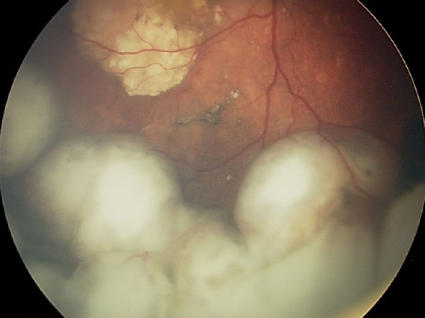

A super resolution image of killer T cells, stained in green and red, surrounding a cancer cell, stained in blue.

A group of killer T cells (green and red) surrounding a cancer cell (blue).

Credit: National Institutes of Health